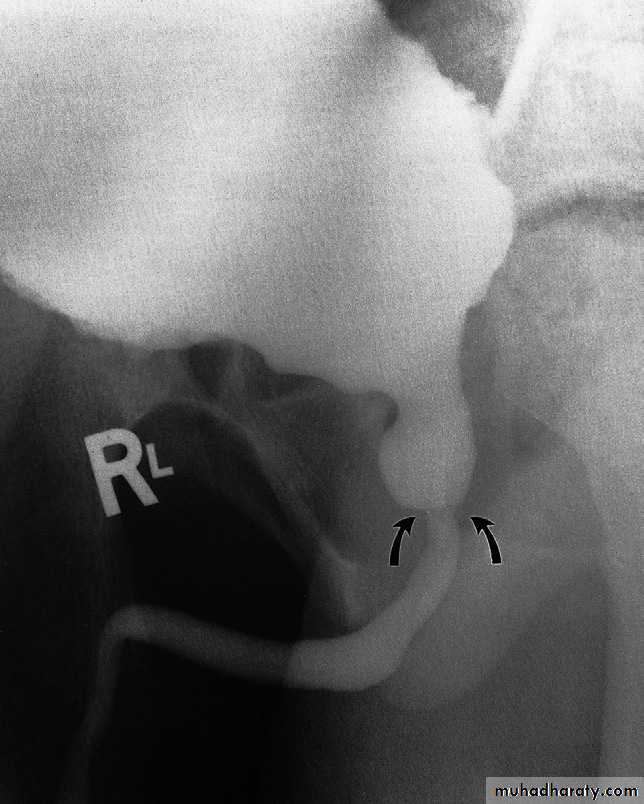

Posterior urethral valves

Congenital valves in the posterior urethra in boys are the commonest cause of bladder outflow obstruction in male children. The diagnosis may be first suspected at antenatal ultrasound, when there is bilateral hydronephrosis. After birth, ultrasound confirms bilateral hydronephrosis and hydroureters and a thick-walled bladder. Urethral valves cannot bedemonstrated by retrograde

urethrography as there is no

obstruction to retrograde flow

but they are easily demonstrated at

micturating cystourethrography